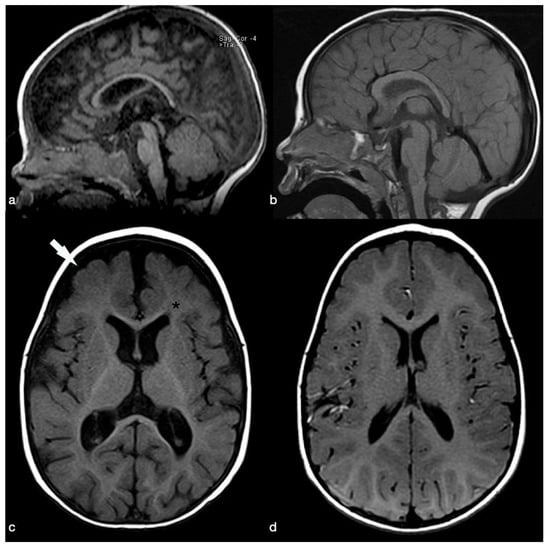

Clinical and Brain Imaging Findings in a Child with Vitamin B12 Deficiency

2. Case Presentation